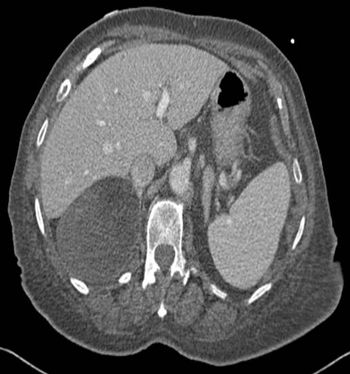

Case History: 62-year-old female with right upper abdominal pain.